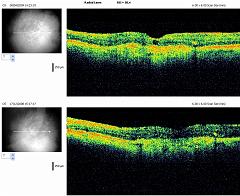

REPERTOIRES ANGIOGRAPHIES

Chaque dossier correspond à un cas dans lequel peuvent se trouver plusieurs examens à des dates différentes.

Path: /3101-20081107-01/08-04-2009/thumbs